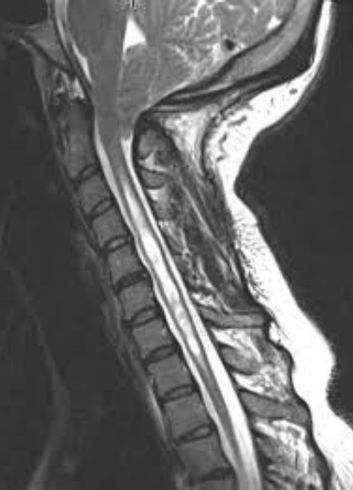

As causas da siringomielia estão frequentemente associadas a outras anomalias, como a malformação de Chiari, ou podem surgir após traumas na coluna, infecções e tumores intramedulares. O diagnóstico preciso é realizado através da ressonância magnética, que permite visualizar a extensão do cisto e o grau de compressão da medula. Esse mapeamento detalhado é o que guia a equipe médica na escolha entre o acompanhamento clínico rigoroso ou a necessidade de intervenção cirúrgica.